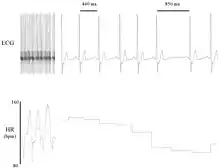

Heart rate variability visualized with R-R interval changes

Electrocardiogram (ECG) recording of a canine heart that illustrates beat-to-beat variability in R–R interval (top) and heart rate (bottom).